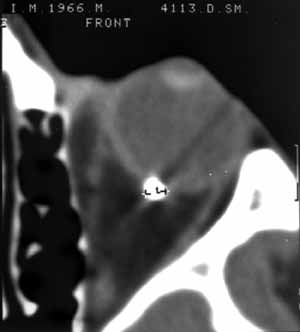

Применение компьютерной томографии в диагностике ранений заднего полюса глазного яблока.

Новости лучевой диагностики 2002 1-2: 40-41